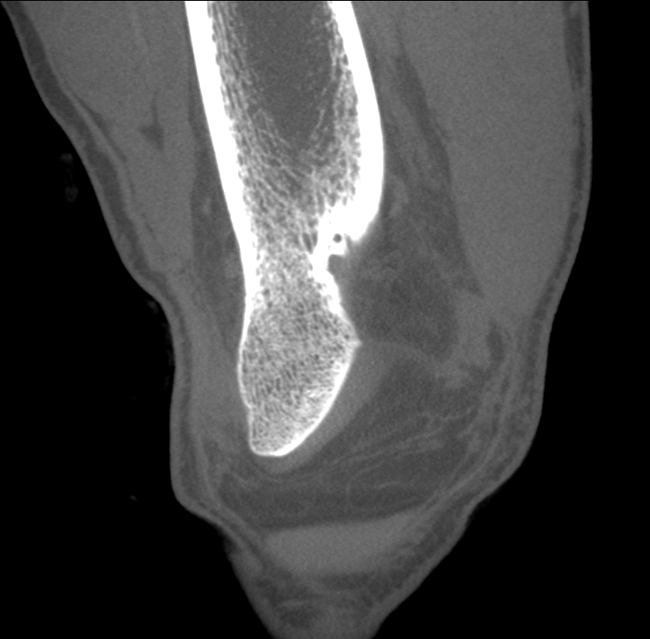

HRCT

High Resolution Computed Tomography. Outstanding image quality with a voxel size up to 100 µm